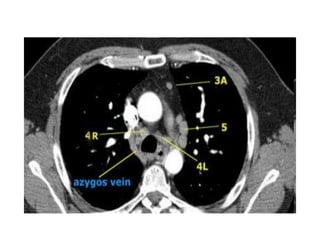

Haïch caïnh khí quaûn döôùi -4R.

4. HAÏCH CAÏNH KHÍ QUAÛN DÖÔÙI

Naèm döôùi ñöôøng ngang veõ tieáp tuyeán bôø treân

cung ñoäng maïch chuû.

4R-Haïch naèm beân (P) ñöôøng giöõa khí quaûn.

4L-Haïch naèm beân (T) ñöôøng giöõa khí quaûn môû roäng ñeán pheá quaûn

chính (T) ôû möùc bôø treân cuûa pheá quaûn thuøy treân (T)-Bao goàm nhoùm

haïch caïnh khí quaûn naèm ôû möùc trung gian ñeán daây chaèng ñoäng maïch.